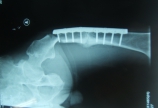

此病例:男,76岁,摔倒外伤,右侧肩关节固定三周入院。入院后影像学检查为: